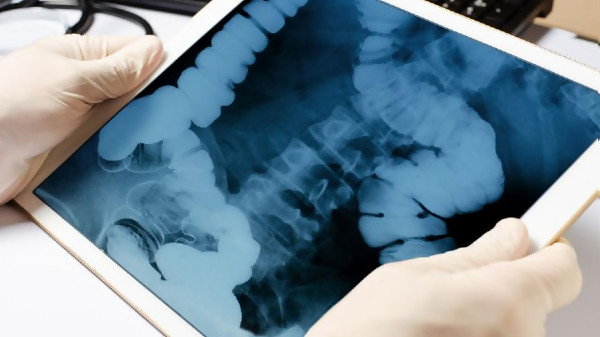

Новозеландски тийнейджър беше опериран, след като е погълнал близо 100 магнита, закупени от сайта за онлайн търговия „Teму“, предаде Франс прес. Тринадесетгодишното момче в продължение на 4 дни изпитвало болки в корема. Детето било отк

Оперираха момче, след като погълнало 100 магнита и те заседнали в червата му

13-годишен погълна близо 100 магнита, претърпя сложна операция